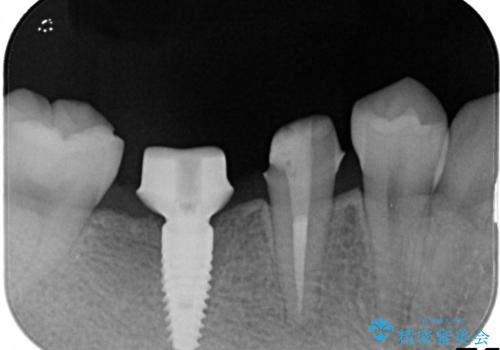

- 右下の奥歯の調子がよくないとのことで来院されました。

レントゲン・口腔内診査をお行い、保存が難しいことがわかりました。

抜歯後インプラントをする計画としました。

見た目では問題がなさそうでも、レントゲン撮影・診査を行うと状態が悪くなっていることがあります。